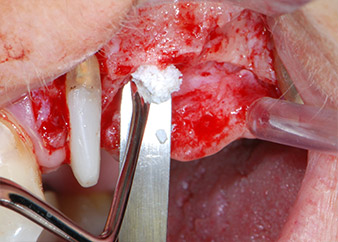

One month later, on the day of surgery, pain and inflammation at tooth 24 were minimal, but mobility of Miller class 2 was still present. After opening the flaps and cleaning the periapical and peri radicular infected tissue, the extent of the bone defect became obvious (Figs. 2 and 3).

At the buccal root, all vestibular and distal bone was missing. Attachment was essentially restricted to the palatal root, underlining the preliminary poor prognosis. Tooth 27 also showed a reduced horizontal attachment and a minimal apical rarefaction (cf. Fig. 1) without clinical symptoms.

total loss of bone and attachment

Fig. 2 and 3: After raising flaps, one month after endodontic revision and initiation of full-mouth periodontal therapy, the buccal root of tooth 24 showed a total loss of bone and attachment.

However, we maintained our initial plan to retain both teeth as temporary bridge abutments during the six-months osseointegration period of the implants. At reentry, the situation would have to be reassessed. First, in an attempt to manage the endo-perio problem, the remaining root surface was carefully debrided with piezoelectric equipment (Piezomed, W&H, used with the spatula-shaped insert S1, originally designed for erosion of the lateral sinus wall) (Fig. 4).